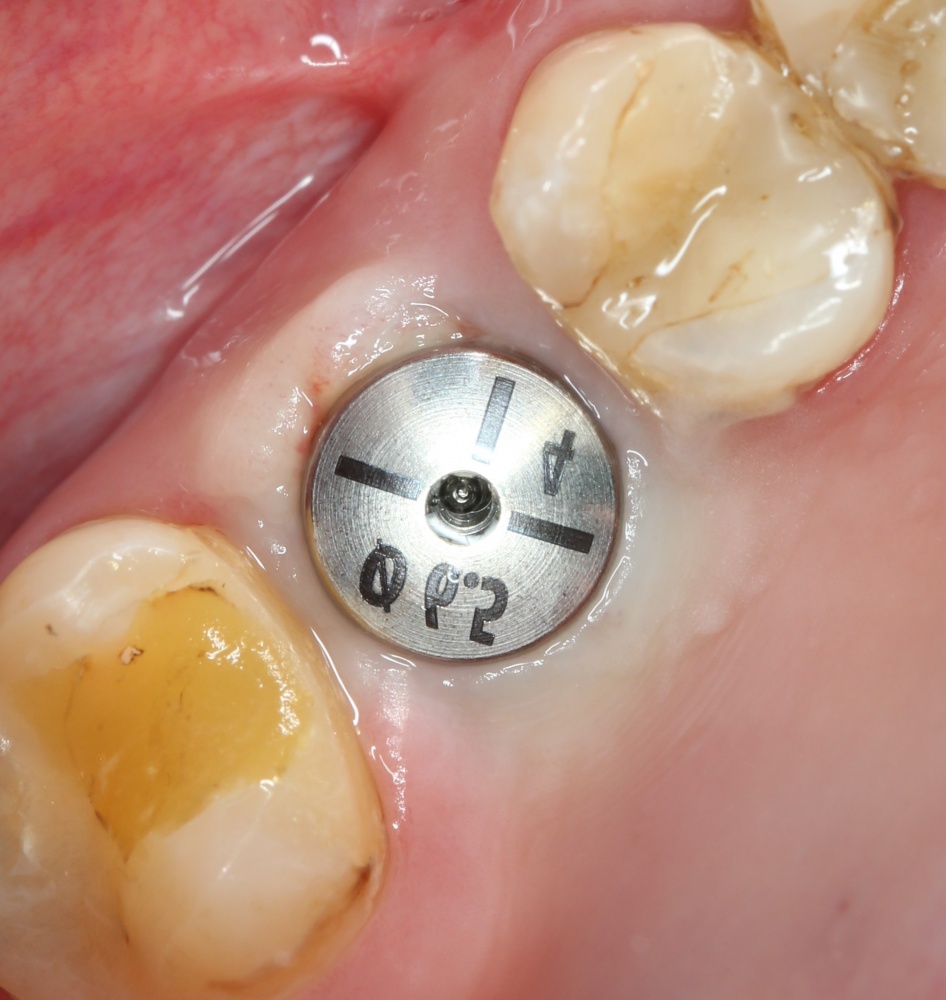

Простой синуслифтинг. Часть I.